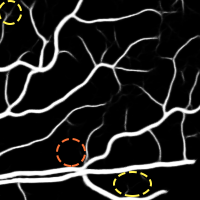

4.1 Validation of the Base System

We started by evaluating our Base System regarding data augmentation, prediction and regularization. The results of each variant are shown in Table 3, while the probabilistic predictions can be seen in Fig. 4. All tests were performed under the same conditions, with the only source of variability being the component under study.

4.1.1 Data Augmentation

To validate the procedure described in Section 2.4, we studied four alternatives. At first, we reduced the total number of patches per image to 3000, by not performing data augmentation – No Augmentation. Then, we increased the total number of patches to 12000 in three different ways. In the first case, we oversampled the image by extracting 9000 more original patches – Oversampling. In the second one, the remaining 9000 patches were artificially created by non-linearly deforming each patch, as described in (Oliveira et al.,, 2017) – Elastic Samples. Each set of 3000 elastic patches was obtained using a different combination: , , or . These values were found manually, ensuring that both the artificial samples and their respective annotations retain a consistent appearance. Finally, we used 9000 rotated patches, as in the Base System, but we placed them consecutively (not randomly) – Consecutive Rotations.

Considering the Base System as the reference, we can see that reducing the number of patches by four strongly deteriorated the results in terms of Acc and AUC. Besides this, either when using original or elastic patches to keep the initial number of samples, the differences to the reference remained almost the same. Looking directly at Fig. 4, we notice that these approaches favored the simultaneous appearance of FN and FP, with elastic patches leading to greater tortuosity in the detected vessel segments. Overall, this hints that the network benefited the most from the information encoded by the rotations. Another important note is related to the way those rotations were presented to the network. Recalling section 2.4, we have seen that some data augmentation strategies designed for FC-CNNs (Dieleman et al.,, 2016; Worrall et al.,, 2016) require the rotated versions to be arranged consecutively. The Consecutive Rotations test hints that a deterministic proximity between the rotated patches is detrimental to the performance of the FCN, with the network showing more difficulties in detecting vessel segments as can be seen in Fig. 4.

4.1.2 Multiple Prediction

After verifying the benefits that the rotated patches brought to the model, we settled out to investigate whether these benefits could be extrapolated to the prediction. Our idea was to synchronously excite the network with the original patches and their rotations, performing the average of the outputs, as described in section 2.4.

Here, we compare the Base System, which uses our multiple prediction scheme, with the Simple Prediction variant. As can be seen in Table 3, the Base System performed better both in terms of Acc and AUC. Moreover, comparing the predictions of both approaches (Fig. 4), we notice that the multiple segmentation scheme makes the model less prone to FP, which is particularly important in medical applications. As a point of note, even if the changes in the mean values were slighter, statistically significant differences were found between the two methods.

4.1.3 Regularization

Finally, we looked at the regularization of the model, by comparing the spatial dropout technique, described in section 2.3.5, with Standard Dropout.

Still having the Base System as a reference, we can see that the standard strategy led to a statistically significant drop in terms of Acc and AUC (Table 3). Overall, the predictions are quite similar, but the model seems to detect fewer vessel segments when the standard dropout is applied (Fig. 4).